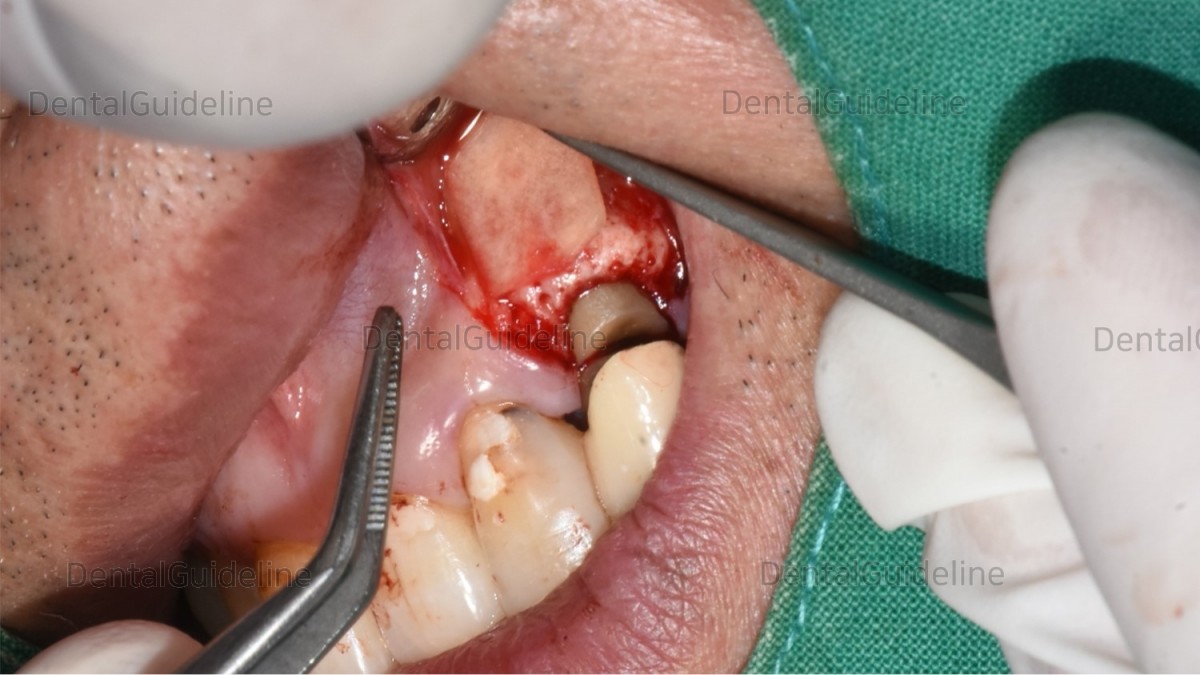

The cut site of the root was filled with MTA (Mineral Trioxide Aggregate).

(It is not visible in this photo due to the shooting angle).

After that, GBR was performed.